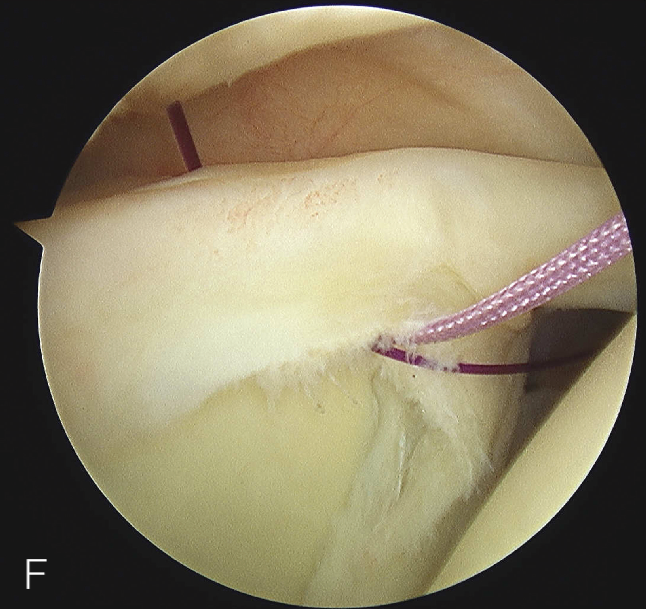

B. 应首先用腰椎穿刺针确定辅助入路的恰当位置和方向。然后在皮肤上做一个小切 A B 口,钻头导向器置入关节。

修复处准备

前方关节囊微紧缩